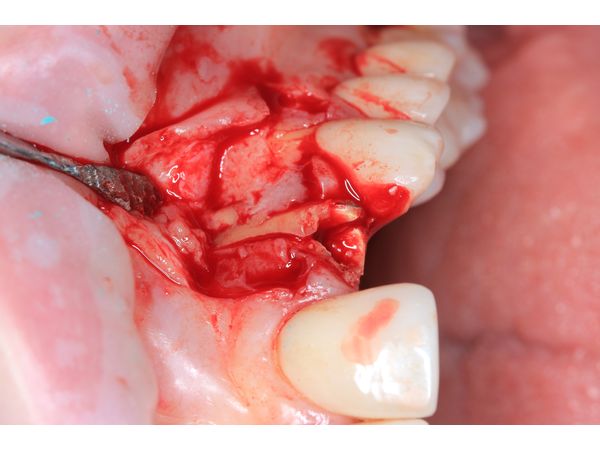

Пациентке сделали анестезию и сформировали микрохирургический доступ для удаления зуба и установки дентального импланта в оптимальную ортопедическую позицию. В зоне дефекта одна треть импланта осталась обнажённой.

Отсутствующую кортикальную пластинку реконструировали с помощью тройного трансплантата из зоны бугра верхней челюсти (забор произвели на стороне вмешательства). Чтобы зафиксировать трансплантат, его утрамбовали в зону дефекта.